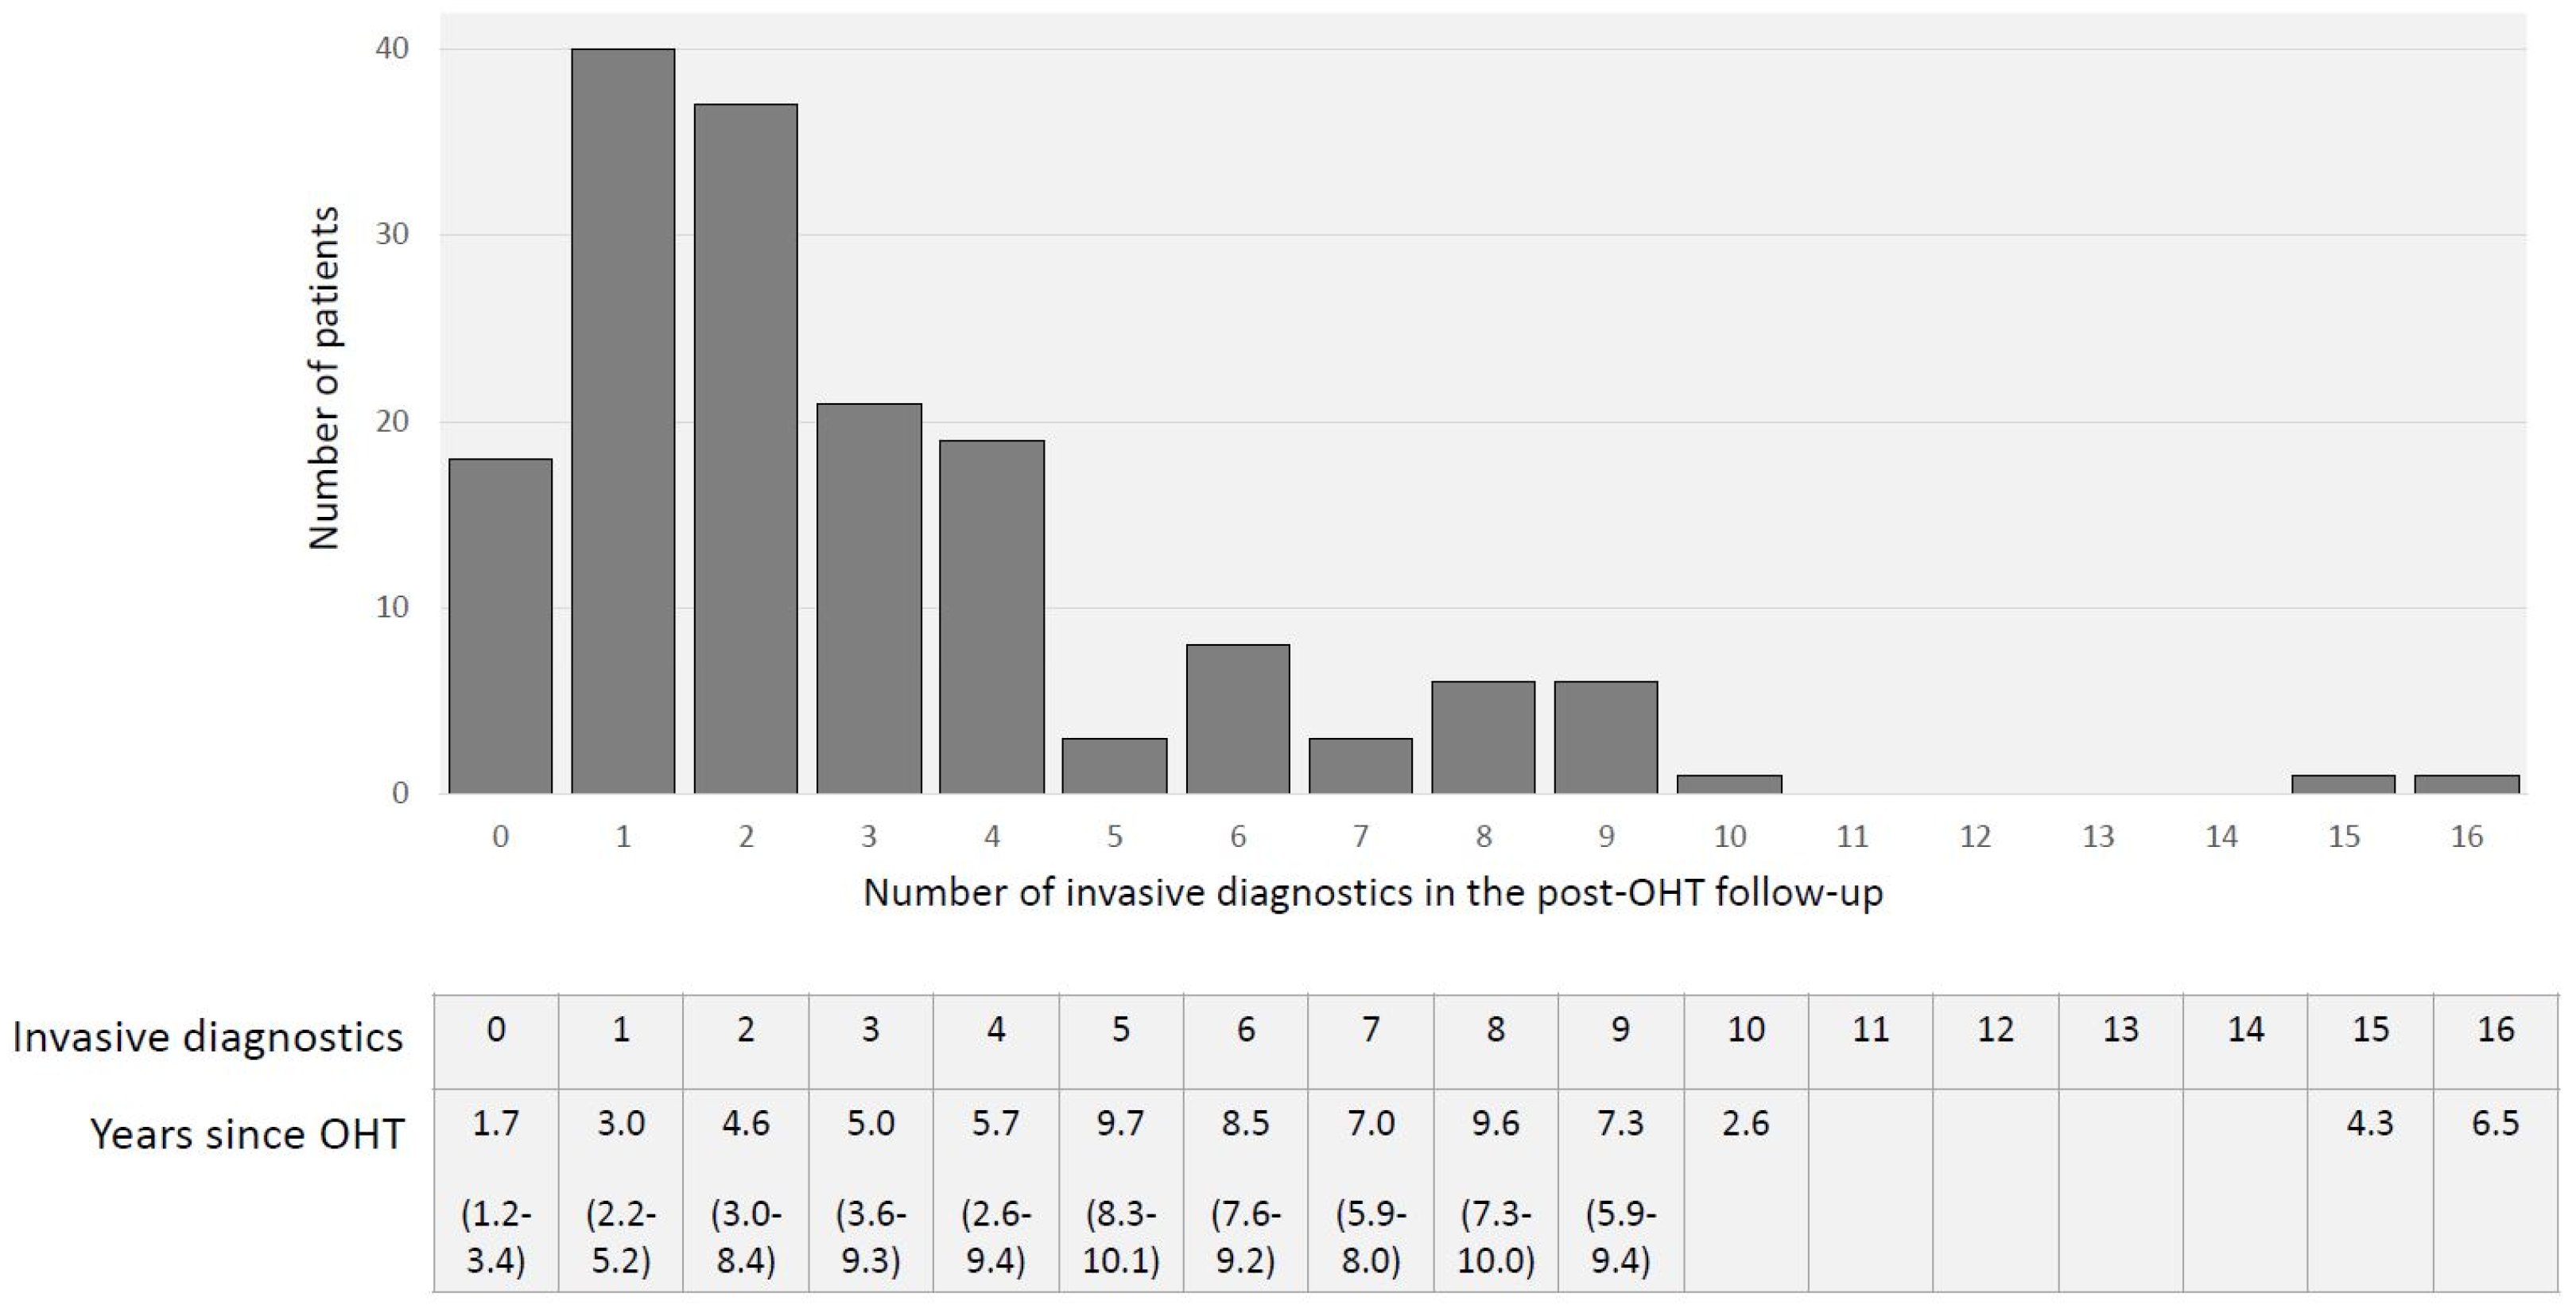

3.2. Invasive Diagnostics in OHT Follow-Up